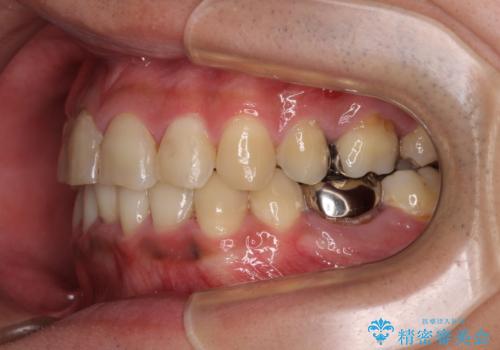

重なって磨きにくい上下の前歯 ワイヤー装置での抜歯矯正

- 前歯のデコボコを改善したいと来院された患者様です。

口元の突出感はないものの、上顎前歯のデコボコが著しかったため、上下顎左右小臼歯4本を抜歯することとしました。

上下の正中位置を改善するため、右下は第一小臼歯を、その他は第二小臼歯を抜歯することとしました。